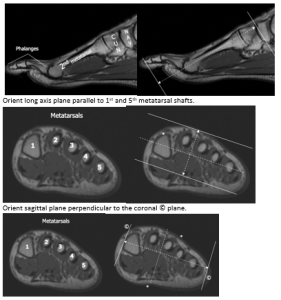

Foot

Orient short axis plane parallel to 2nd/3rd metatarsal shaft.

Orient long axis plane parallel to 1st and 5th metatarsal shafts.

Orient sagittal plane perpendicular to the coronal © plane.